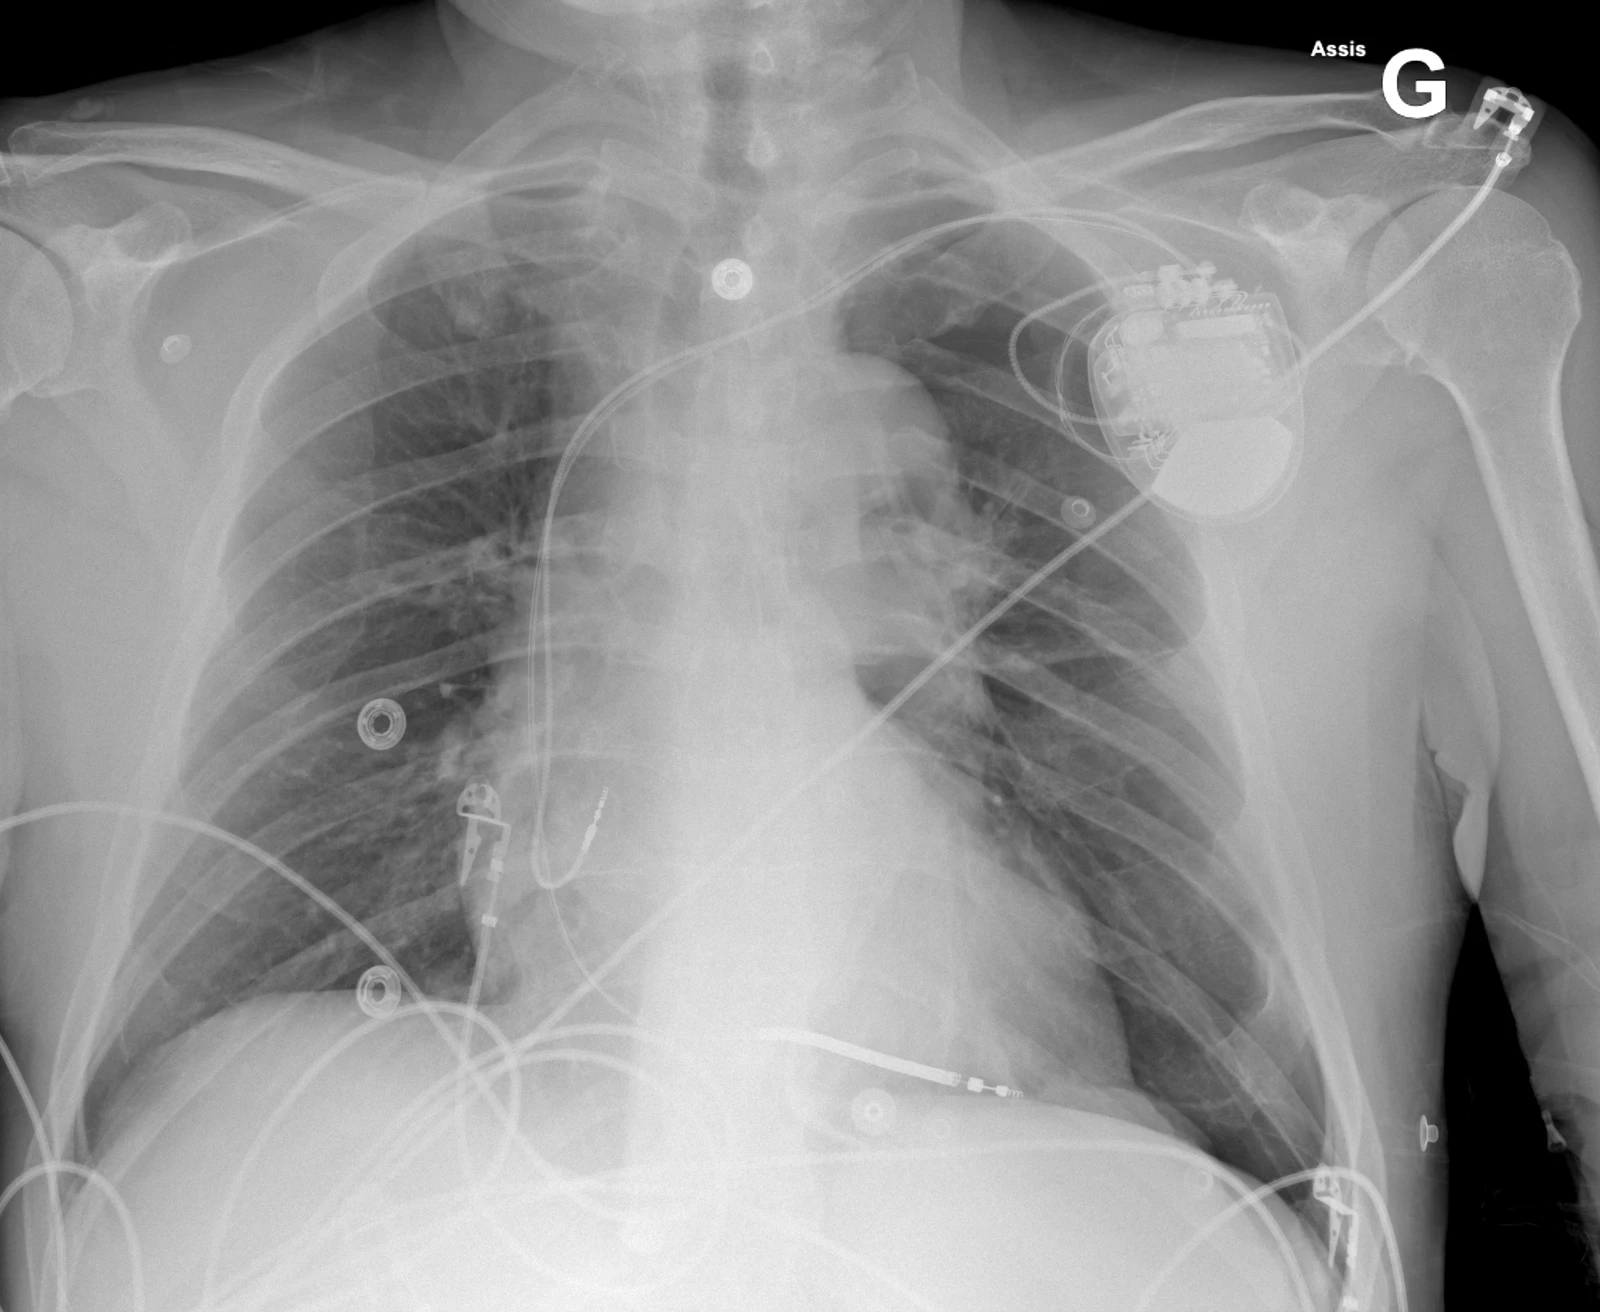

Cette radiographie du thorax a été faite chez un patient se plaignant de douleur thoracique gauche quelques heures après la pose d’un pacemaker (PM). Plusieurs complications peuvent survenir après la pose d’un PM. Le pneumothorax est une complication de l’accès vasculaire lors de l’implantation avec une fréquence de 0.9-1.3%. Les facteurs de risques sont l’âge (> 80 ans), sexe féminin, BPCO sous-jacente, PM double chambre. Le pneumothorax est une complication qui survient durant la pose du PM mais peut ne pas être reconnue immédiatement. Les patient·es se présentent avec des douleurs thoraciques respiro-dépendantes ipsilatérales au boitier du PM et une dyspnée.  Le traitement dépendra de la taille du pneumothorax et des comorbidités de la ou du patient·e. Les petits pneumothorax (< 2 cm) sont plutôt traitement conservativement. En général, un pneumothorax de > 2 cm devra être drainé.